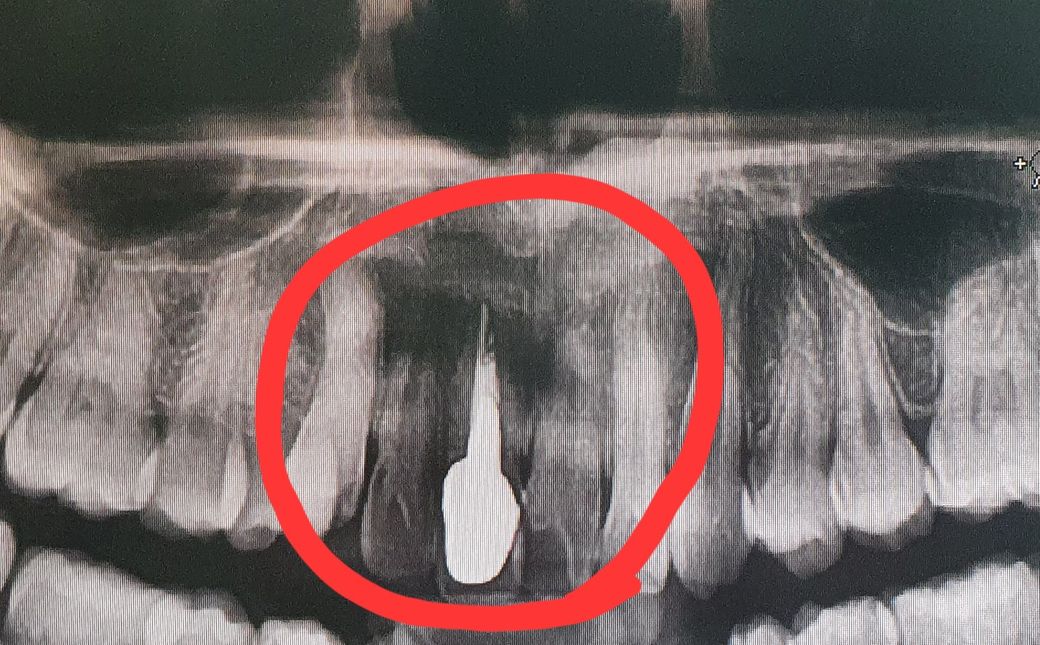

사랑니 발치때문에 x-ray를 찍었는데 동그라미 친부분만 유독 잇몸이 까맣게 보이는 이유가 뭘까요?? 그리고 사진상 보철치료? 한곳 왼쪽에 있는 이는 뿌리가 짧은건가요?? 치과에서는 별말씀 없으셨는데 보다보니 이상한것같아서요

앞니 부분이 더 검은 이유는 해당 부위의 뼈 두께가 어금니쪽에 비해 얇아 상대적으로 방사선이 더 많이 투과되어 검게 변하는 경우 등의 원인이 있습니다.

• 안녕하세요. 정진석 치과의사입니다.

방사선 사진에서 밀도가 큰 물질은 하얗게 보이고 밀도가 작은 곳은 까맣게 보이게 됩니다. 따라서 해당 공간에 밀도가 적을 경우에는 까맣게 나타날 수 있습니다. 물론 말씀하신 부위는 비어 있는 것은 아니며 방사선 관구가 조사되는 각도에 나타나는 현상일 수 있습니다. 현재 사진으로는 정확한 판단은 힘들며 파노라마 사진은 3차원을 2차원으로 구현하므로 상당한 왜곡을 보이게 됩니다. 따라서 실제로 공간이 비어있지 않지만 까맣게 보이거나 촬영각도에 따라 치아들이 짧아보이거나 할 수 있습니다.

엑스레이는 빈공간은 검정색으로 나타나게 됩니다. 위 앞니 부분은 비강 즉 콧구멍이 잇는곳이라 사진을 찍으면 저렇게 나올수 있으며 뿌리는 비강이랑 겹차면서 사진상에 그렇게 보이는거 같습니다.

동그라미 친 부분에 잇몸이 까맣다고 하셨는데, 엑스레이상으로 잇몸이 여기에서 보이진 않습니다. 어느부위를 말씀하시는지 정확히 모르겠으나, 중간부분에 검정색 음영이 있는 부위를 의미하는 것이라면, 그 부위의 뼈의 밀도가 낮아서 그렇게 보일수도 있고, 파노라마사진이 돌아가면서 찍는것이기 때문에 사진상 그렇게 나온것일 수도 있습니다.